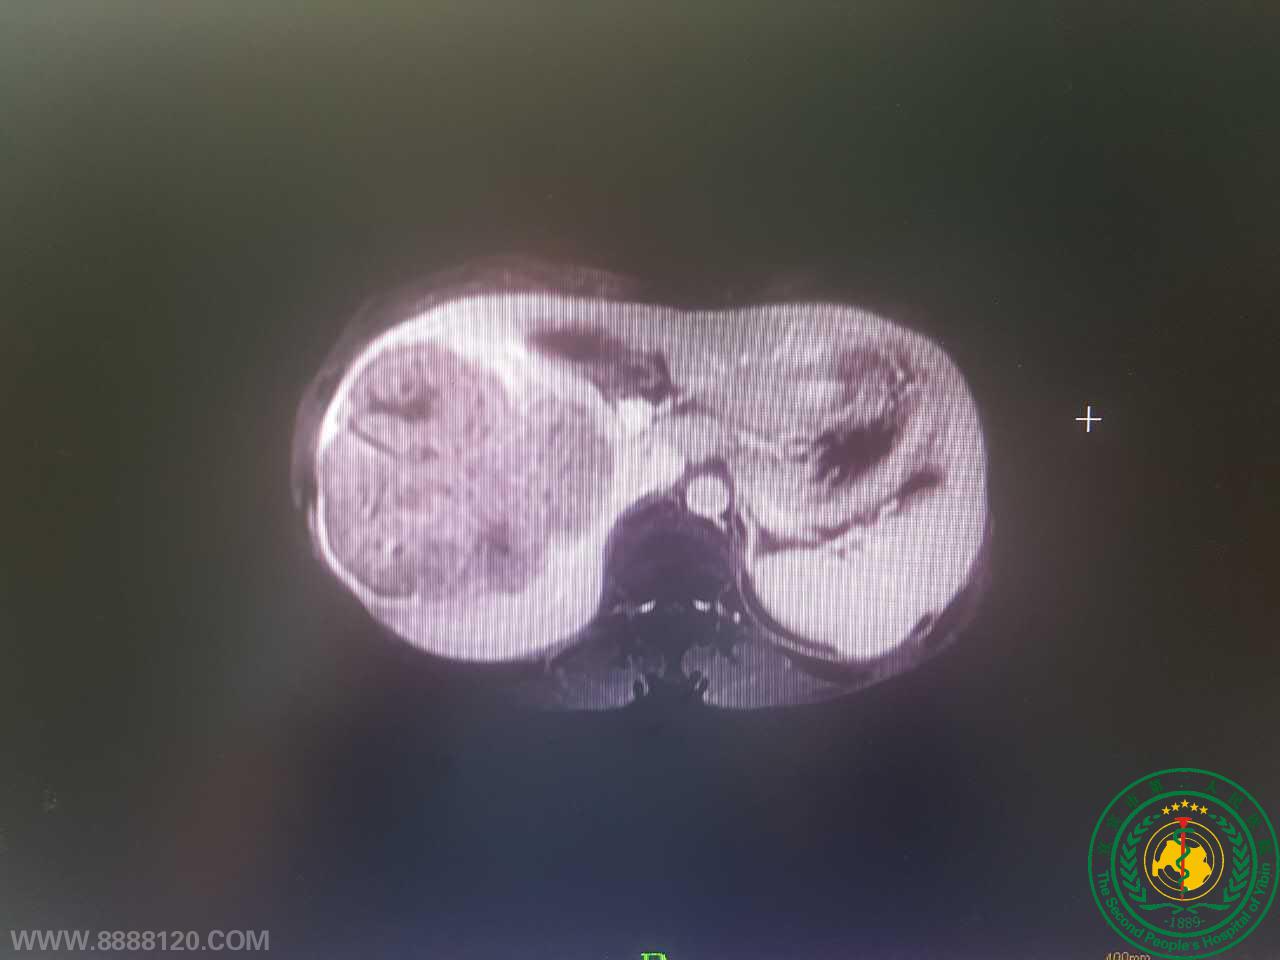

2017年08月07日,宜宾市二医院肝胆胰外科在麻醉科及手术室的配合下,为一例右肝巨大肝癌男性患者顺利完成了宜宾市第一例完全腹腔镜下前入路标准右半肝切除术。

术中采用精准断肝技术,未阻断全肝入肝血流,但出血少,未输血,对残肝功能影响降到最低。

采用前入路原位逆行切除方法,不需翻动挤压肝脏,降低了肿瘤播散转移风险。